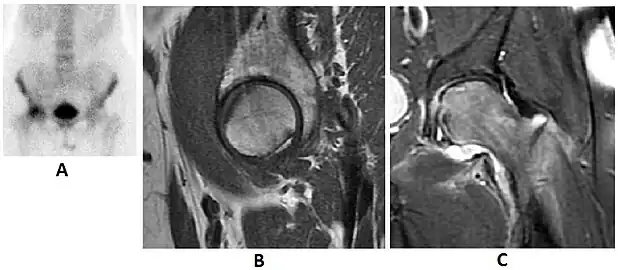

Scintigraphy (A), sagittal T1 (B), and coronal PD fat sat of a patient with a subchondral fracture of the femoral head with convex shape to the articular surface.[1] -

Coronal T1 of a patient with avascular necrosis of the femoral head.[1]